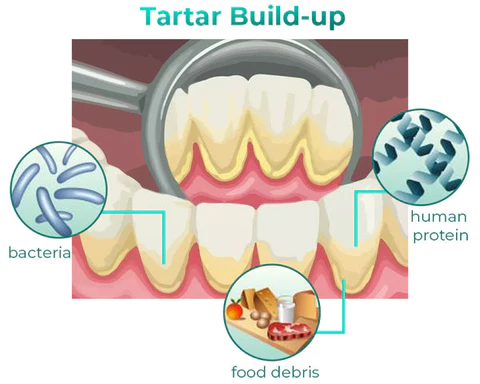

Removes tartar plaque and other oral problems. Get the confidence you deserve!

TLOPA™ Ampoule Oral Restorative Toothpaste can thoroughly whiten yellow teeth, remove tartar accumulated on teeth, solve dental plaque, and bring a comprehensive and clean oral experience. Remove bad breath, relieve tooth sensitivity, gum bleeding, etc. Solve tooth sensitivity and gum bleeding, repair gum damage and receding gums.